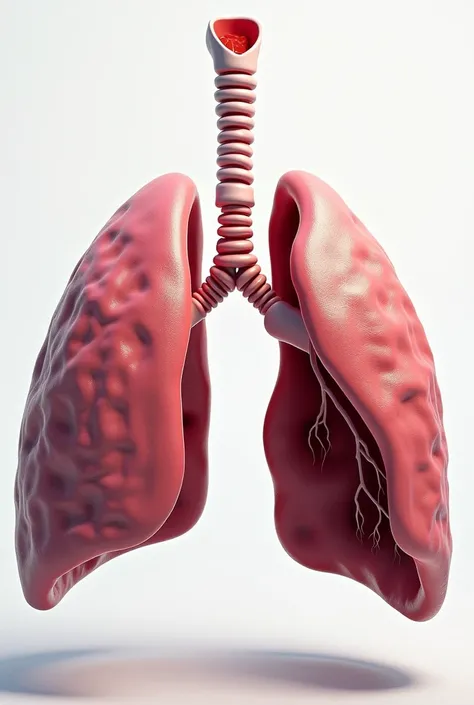

Make a folder about bacterial pneumonia

Make a folder about bacterial pneumonia

Make a folder about bacterial pneumonia